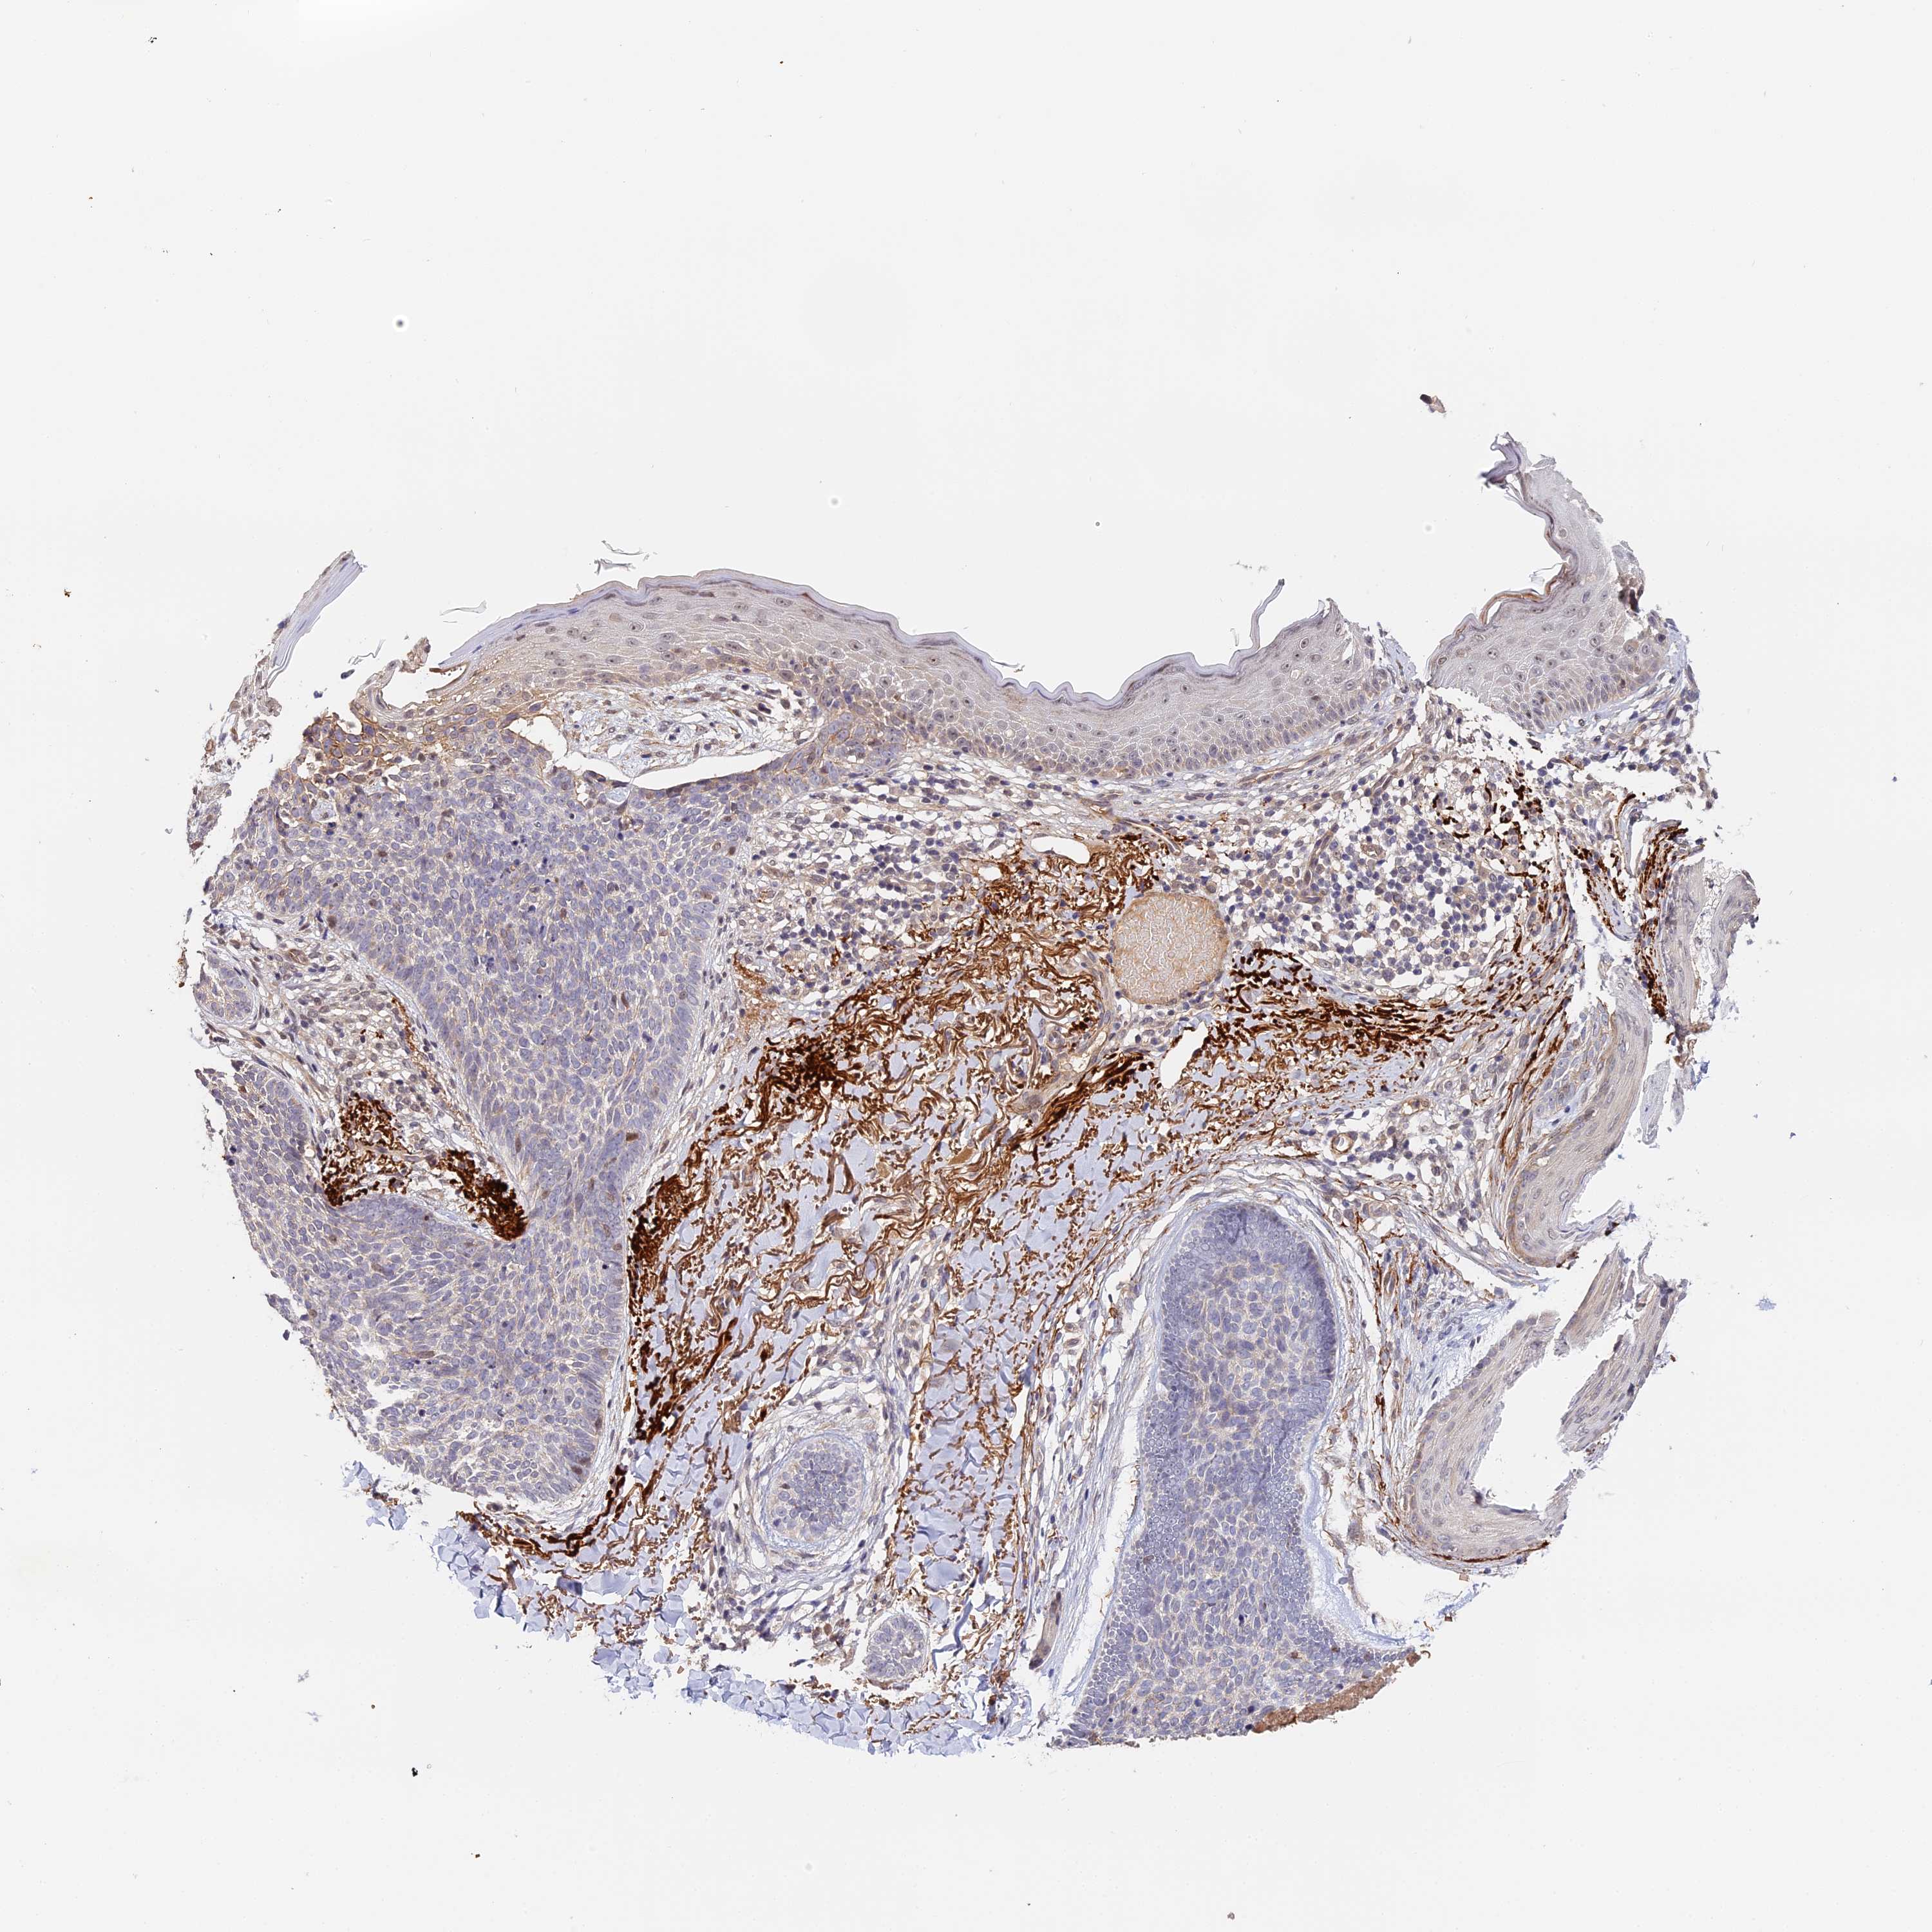

SKIN CANCER - Protein expressioni

A mouse-over function shows sample information and annotation data. Click on an image to view it in a full screen mode. Samples can be filtered based on level of antibody staining by selecting one or several of the following categories: high, medium, low and not detected. The assay and annotation is described here.

Antibody stainingi

Antibody staining in the annotated cell types in the current human tissue is reported as not detected, low, medium, or high, based on conventional immunohistochemistry profiling in selected tissues. This score is based on the combination of the staining intensity and fraction of stained cells.

Each image is clickable and will lead to virtual microscopy that enables deeper exploration of all samples and also displays staining intensity scores, fraction scores and subcellular localization as well as patient and tissue information for each sample.

Antibody HPA041045

Antibody HPA041968

Squamous cell carcinoma, NOS

Basal cell carcinoma